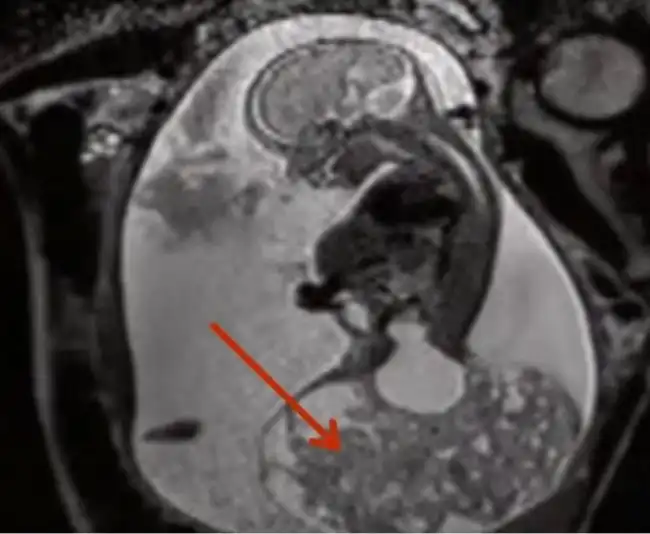

Американка Кери Маккартни (Keri McCartney), мать четверых детей, была беременна пятым ребенком и на 23-й неделе беременности захотела узнать пол малыша. По результатам УЗИ выяснилось, что у плода образовалась большая доброкачественная опухоль, которую решено было удалить. Как проходила эта сложнейшая операция, шансы на успех которой составляли 10%, читайте далее.

Опухоль почти достигала размеров плода и забирала у него все жизненные силы, нарушая кровоток. Провести такую операцию, не прерывая беременность, казалось невозможным, но врачи справились. Кери ввели в наркоз, оказавшийся в 7 раз глубже обычного, добились полного расслабления матки и полностью извлекли ее из брюшной полости. Хирургам удалось вскрыть матку и не повредить при этом плаценту. Плод извлекли через сделанный разрез, оставив в полости матки только его голову. 20 минут потребовалось на то, чтобы удалить опухоль и поместить плод обратно. Вся операция длилась 4 часа и закончилась успешно. Спустя 10 недель на свет появилась девочка Мэйси-Хоуп, второе имя которой в переводе с английского означает «надежда».